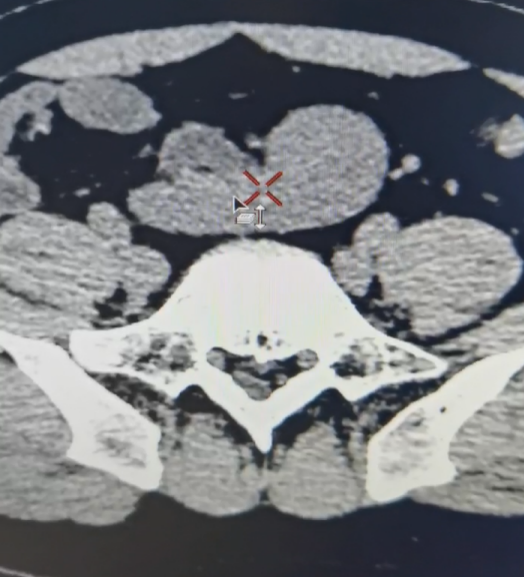

患者男,22岁,因“查体发现异位肾4年,左下腹疼痛1周”就诊,无尿频尿急尿痛,无肉眼血尿等其他临床症状,B超检查显示左侧异位肾,肾盂肾盏积水。行逆行造影检查显示左肾异位,左肾盂明显积水。行CTA(CT血管造影)检查显示左肾区空虚,盆腔内见异位肾体,异位肾门朝前。右侧髂总动脉及肠系膜下动脉发出分支分布于异位肾,异位肾静脉汇入下腔静脉下段,异位肾肾盂明显扩张。行ECT(利用放射性核素的检查方法)检查显示GFR:左肾8.88ml/min,右肾49.45ml/min,总值58.33ml/min。考虑患者左肾功能受损伴下腹部疼痛,遂行达芬奇机器人辅助腹腔镜左侧异位肾肾盂成形术。

术后6周复查患者疼痛消失,查血显示尿素氮 4.30 mmol/L,肌酐 92 μmol/L,肾小球滤过率 101.350 ml/min,CT显示肾盂积水明显减轻。